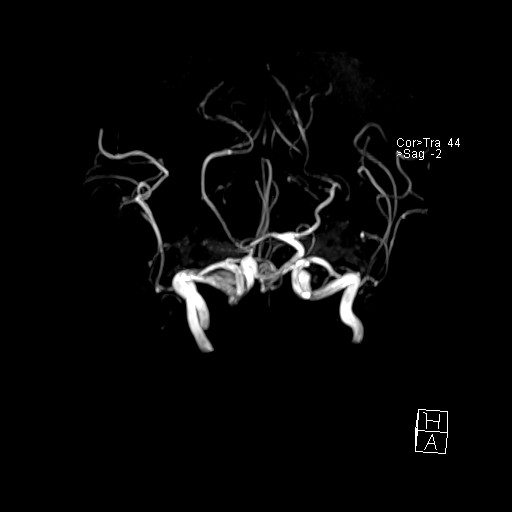

- VILLANUEVA, WILLIAM A. MR HEAD

- VILLANUEVA, WILLIAM A. MR HEAD

- VILLANUEVA, WILLIAM A. MR HEAD

- VILLANUEVA, WILLIAM A. MR HEAD

- VILLANUEVA, WILLIAM A. MR HEAD

- VILLANUEVA, WILLIAM A. MR HEAD

- VILLANUEVA, WILLIAM A. MR HEAD

- VILLANUEVA, WILLIAM A. MR HEAD

- VILLANUEVA, WILLIAM A. MR HEAD

- VILLANUEVA, WILLIAM A. MR HEAD

- VILLANUEVA, WILLIAM A. MR HEAD

- VILLANUEVA, WILLIAM A. MR HEAD

- VILLANUEVA, WILLIAM A. MR HEAD